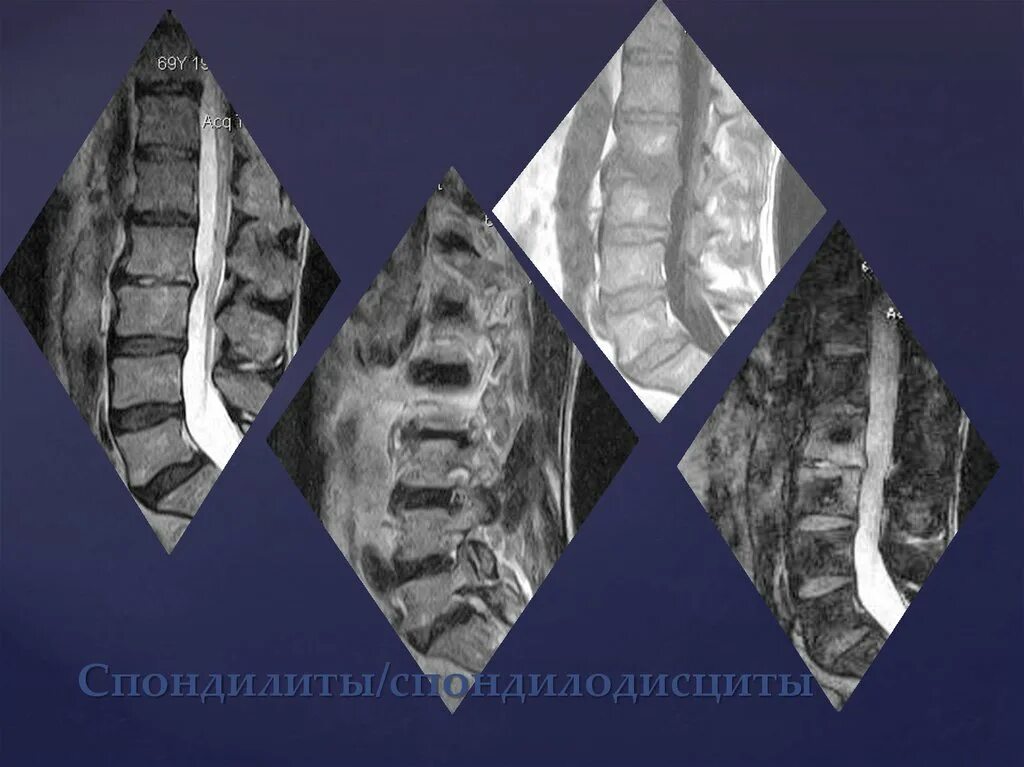

Modic тип 1